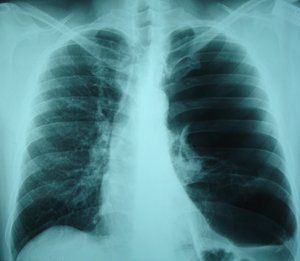

Εικόνα 1.

Οπισθιοπροσθία ακτινογραφία θώρακος. Διακρίνονται ευμεγέθεις

αερώδεις κύστες που καταλαμβάνουν, σχεδόν ολόκληρο το αριστερό

ημιθωράκιο. Ο ασθενής είχε αίσθημα δύσπνοιας μετά από προσπάθεια.